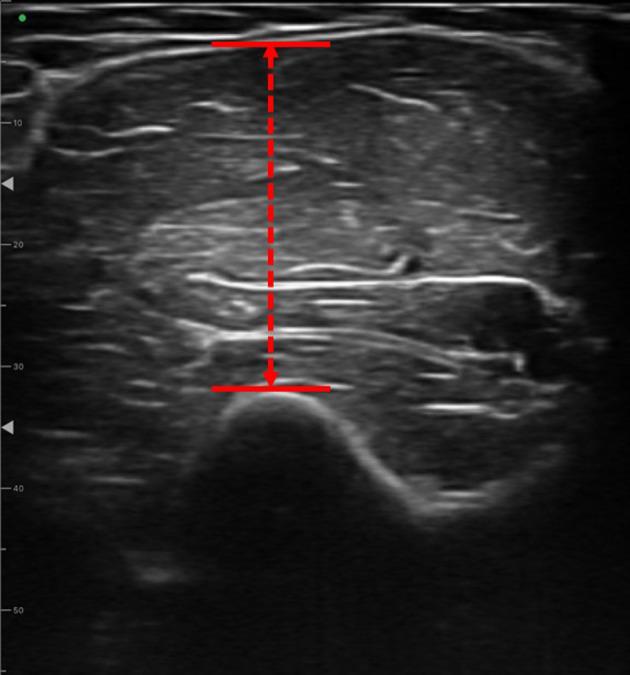

[Purpose] Optimization of post-training muscle recovery is important in clinical rehabilitation and sports science. In this study, we investigated the effects of local vibration stimulation on post-training muscle recovery and hypertrophy in healthy adults, focusing on the upper extremities. [Participants and Methods] The study included 20 healthy students categorized into the control and vibration stimulation groups. Both groups underwent training, including elbow flexion. The vibration stimulation group received immediate post-training local vibration stimulation. Evaluation included measurement of upper arm circumference, muscle strength, muscle hardness, and ultrasonographic imaging. [Results] Our results showed that local vibration stimulation increased muscle luminosity but had no significant effect on muscle strength, hardness, or thickness. [Conclusion] Post-training vibration stimulation may promote muscle growth and recovery by stimulating blood flow and improving nutrient and oxygen supply to muscles.

[目的] 优化训练后肌肉恢复在临床康复和运动科学中至关重要。在本研究中,我们调查了局部振动刺激对健康成年人训练后肌肉恢复和肥大的影响,重点关注上肢。[参与者和方法] 该研究纳入了20名健康学生,分为对照组和振动刺激组。两组均进行了包括肘部屈曲的训练。振动刺激组在训练后立即接受局部振动刺激。评估包括测量上臂围、肌肉力量、肌肉硬度和超声成像。[结果] 我们的结果表明,局部振动刺激增加了肌肉亮度,但对肌肉力量、硬度或厚度没有显著影响。[结论] 训练后振动刺激可能通过刺激血流和改善肌肉的营养和氧气供应来促进肌肉生长和恢复。